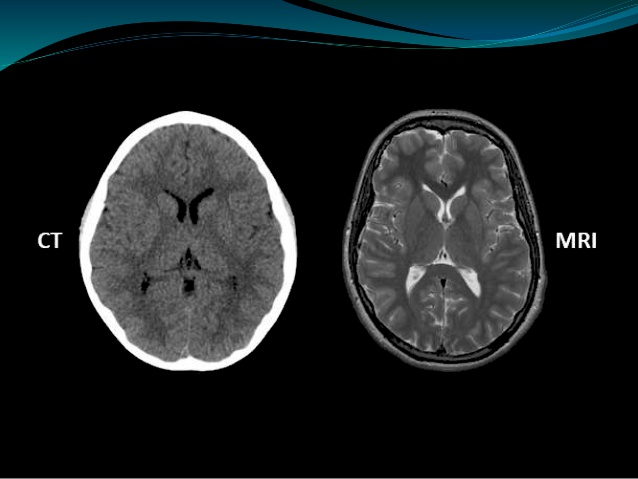

A CT scan vs and MRI scan. From Ajay Nagisetti’s presentation of CT Scan vs MRI Scan on Slideshare